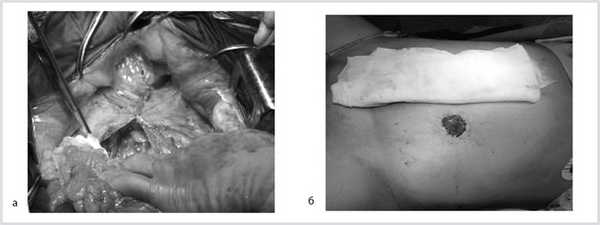

07.11.2012 выполнена цилиндрическая или экстралеваторная экстирпация прямой кишки. Через тазовую брюшину в мезоректальной клетчатке справа пальпируется верхний полюс опухоли, подрастающей к стенке прямой кишки, опухоль фиксирована к правой боковой стенке таза. Отдаленных метастазов нет (рис. 4).

Рис. 4. Этап операции. Ревизия опухоли.

Произведена мобилизация прямой кишки по левой и задней полуокружности, а также пресакрально до мышц тазового дна с соблюдением всех онкологических правил (рис. 5). По левой боковой стенке таза опухолевая капсула интимно прилежит к внутренней подвздошной вене и артерии, острым путем последняя мобилизована от магистральных сосудов.

Рис. 5. Этапы операции. а — мобилизация слева; б — мобилизация справа.

Далее сигмовидная кишка пересечена на уровне ее дистальной трети, а прямая кишка погружена в малый таз, при этом тазовая брюшина ушита над заглушенной культей прямой кишки. Затем сигмовидная кишка забрюшинно выведена в левом боковом отделе живота на переднюю брюшную стенку и сформирована плоская колостома, после чего брюшная полость ушита наглухо послойно (рис. 6).

Рис. 6. Этапы операции. а — ушивание тазовой брюшины; б — сигмостома.